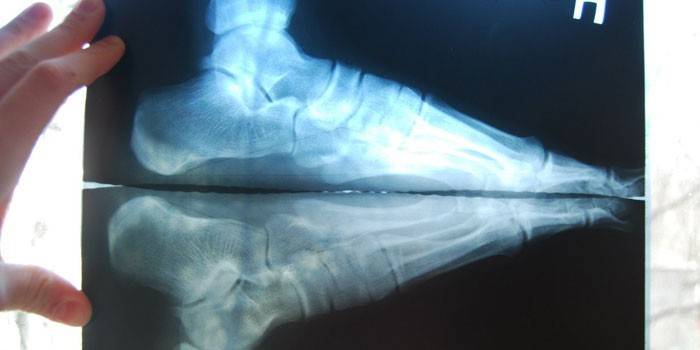

- Fasciitída je plantárna. Iné meno pre túto chorobu je všeobecne známe - podrážka päty. Zápalový proces sa vytvára na vláknitom väze podporujúcom oblúk chodidla. Ochorenie sa vyskytuje s nadmerným rozťahovaním alebo stresom na túto štruktúru. Nárast bolesti sa zosilňuje, symptóm sa ráno zvyšuje. Na identifikáciu ochorenia a vylúčenie zlomenín alebo prasklín sa vykoná rôntgenové žiarenie.

- X-ray - štúdia zameraná na stanovenie viditeľných špecifických zmien charakteristických pre konkrétnu patológiu;